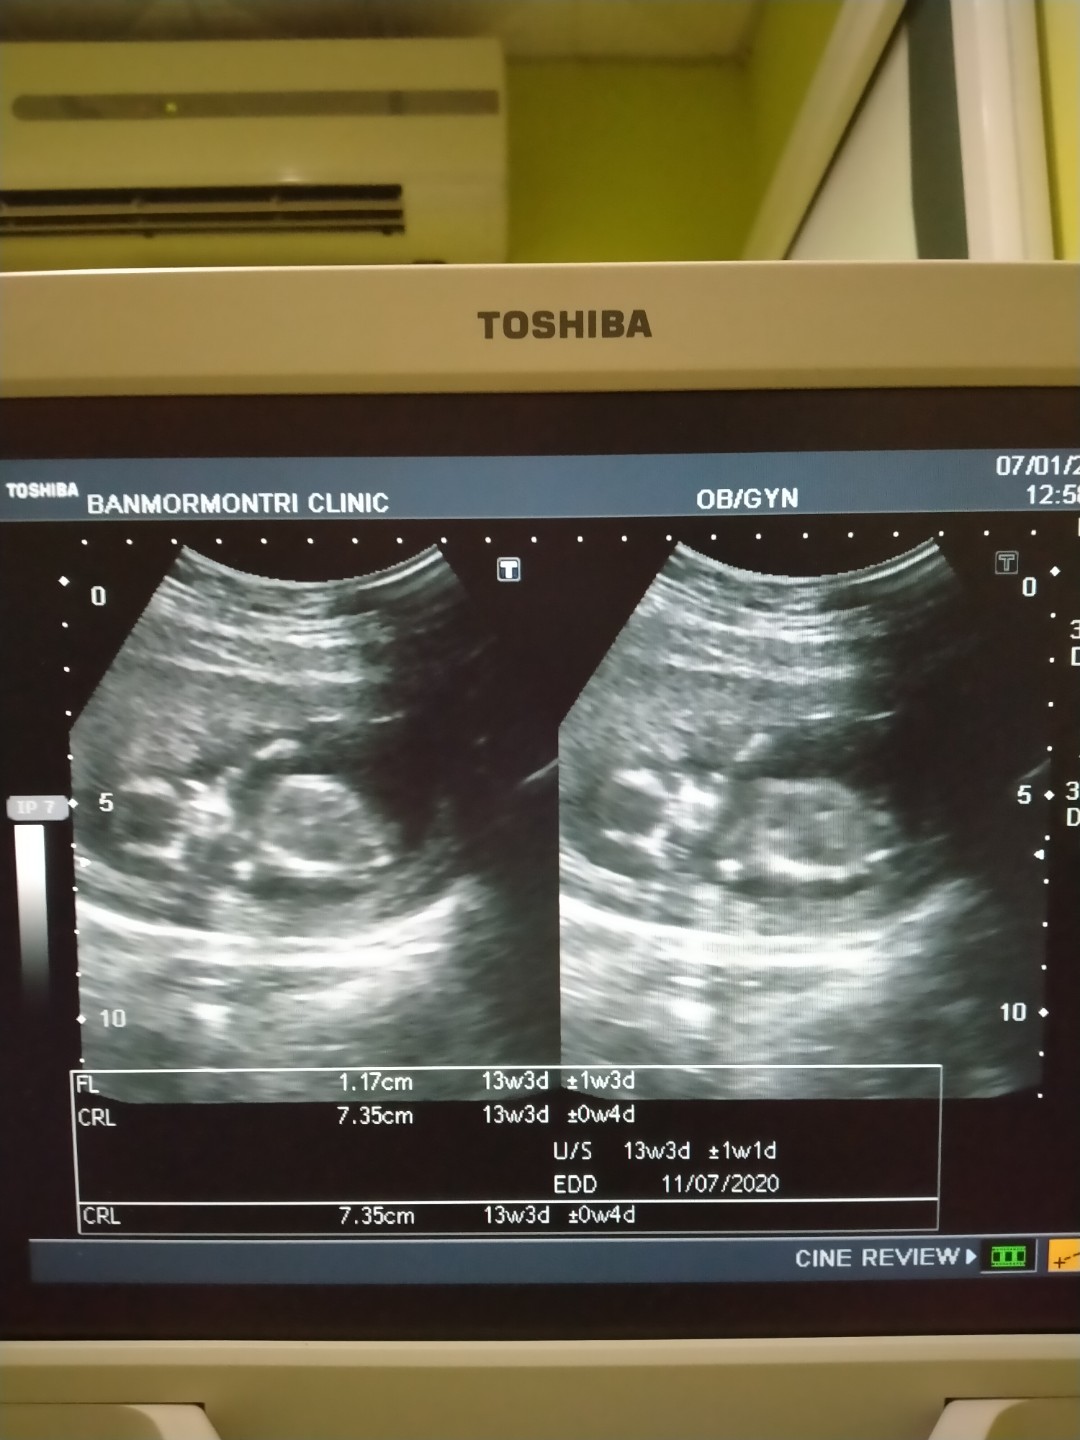

07 กรกฎาคม 63 เพศ ชาย ค่ะ